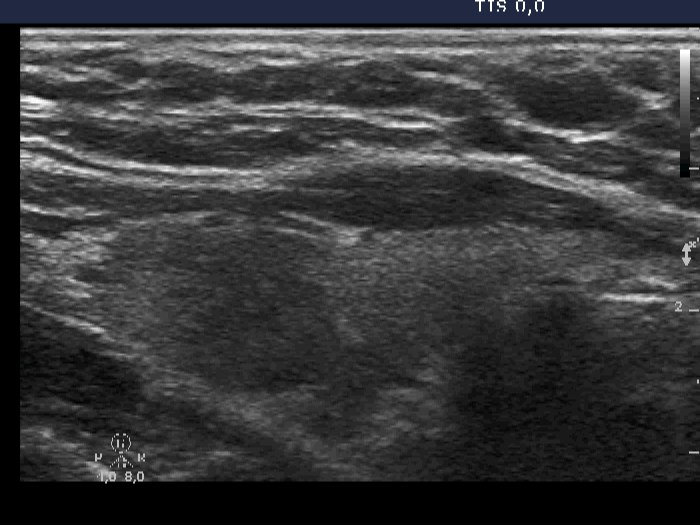

Case 316 (ultrasonographic picture 2)

Right lobe, longitudinal scan. Minimally hypoechogenic areas are demonstrated.